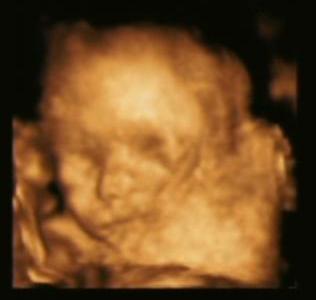

igen már tudjuk, kislány lesz. Orsolya, Mária. Már nagyon várjuk. Kép Pocaklakó

Ez a fotó december 14 -én készült.